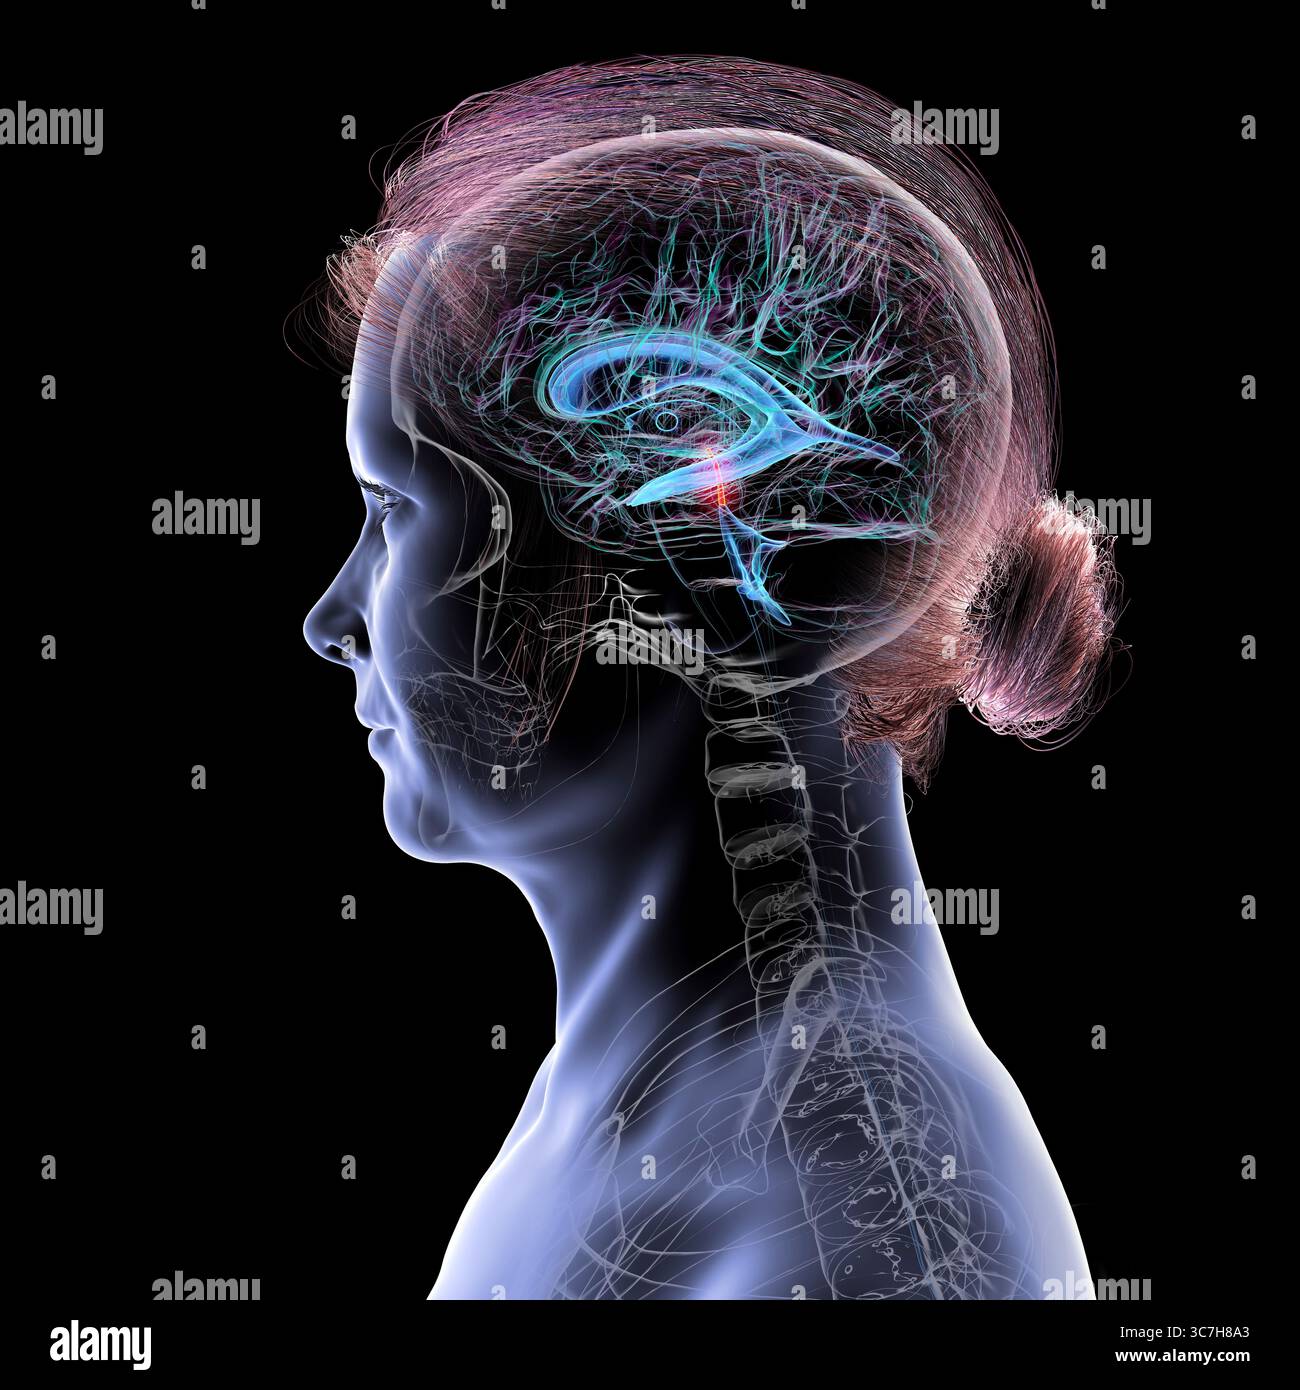

RF3C7H8A6–Abbildung des Gehirns mit hervorgehobenem Aquädukt (rot) und ventrikulärem System (blau), Darstellung des Liquorflusses.

RF3C7H8AA–Abbildung des Gehirns mit hervorgehobenem Aquädukt (rot) und ventrikulärem System (blau), Darstellung des Liquorflusses.

RF3C7H8AF–Abbildung des Gehirns mit hervorgehobenem Aquädukt (rot) und ventrikulärem System (blau), Darstellung des Liquorflusses.

RF3C7H8A3–Abbildung des Gehirns mit hervorgehobenem Aquädukt (rot) und ventrikulärem System (blau), Darstellung des Liquorflusses.